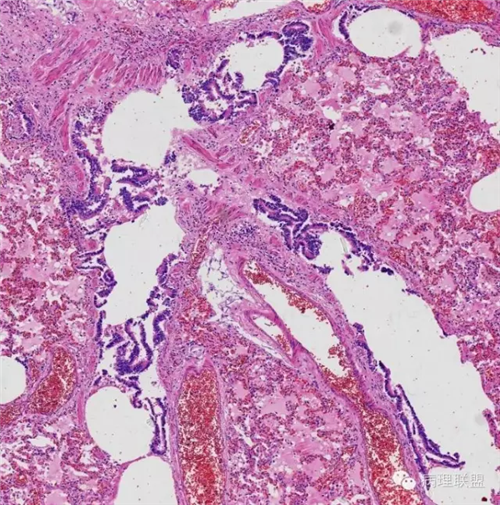

肺的

不仅仅是肺水肿

▲病例由南方医科大学病理教研室邓永键教授提供,致谢!▲